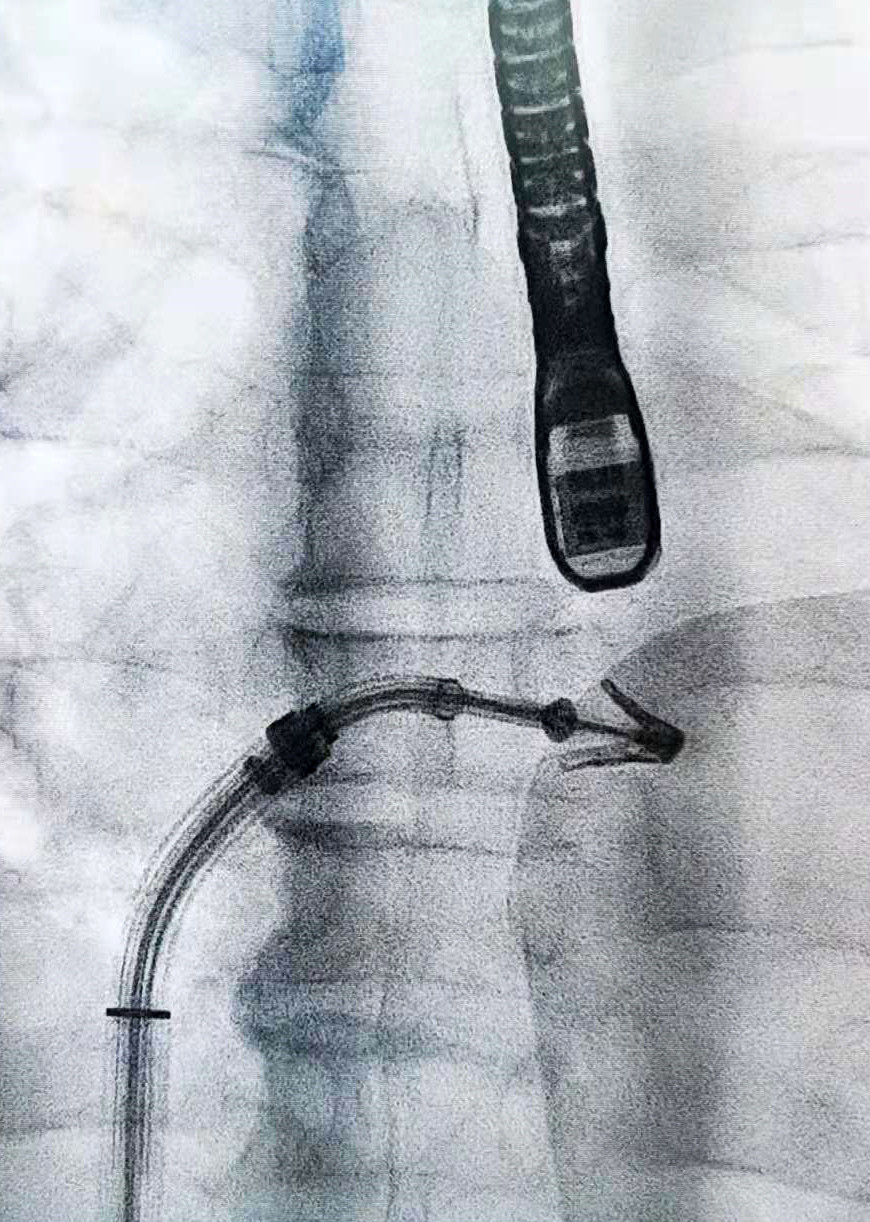

王焱教授(右一)率团队实施我国首例二尖瓣机械瓣术后的Venus A Plus瓣膜植入。

心脏瓣膜团队不满足于此,他们紧随国际医学前沿,运用先进治疗方案,挑战高难度病例。今年,微创瓣膜手术进一步得到完善:2月,团队运用我国首个可回收瓣膜系统——Venus A Plus瓣膜为已多次进行心脏手术的老人更换瓣膜,完成了我国首例二尖瓣机械瓣术后的Venus A Plus瓣膜植入;3月,采用经皮穿刺微创介入方案为生命垂危的七旬老人进行联合双瓣膜置换术,在同一台手术中更换了主动脉瓣膜和二尖瓣膜,全国尚属首例;4月,在省内率先完成经导管二尖瓣钳夹术,成为中国大陆第五家开展该项技术的医院。

经导管主动脉瓣膜置换术(TAVI手术)采用的支架状如莲花,内部附有生物瓣膜。